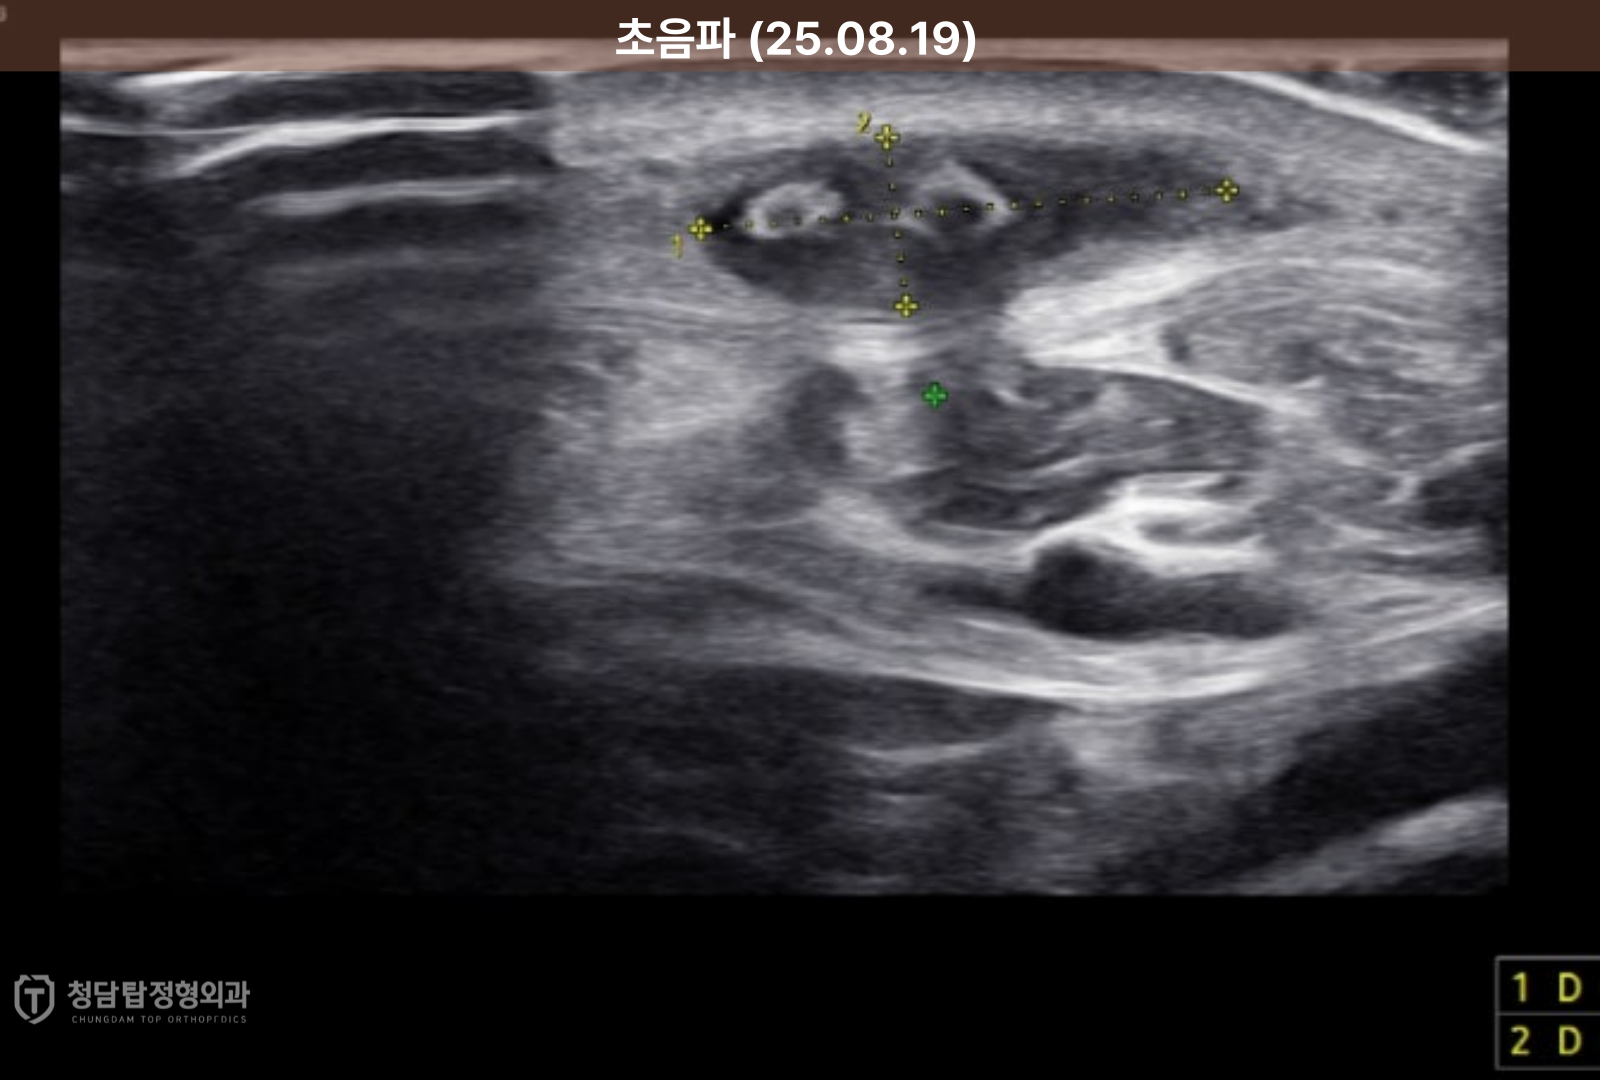

초음파 화면에는 약 3~4mm 크기의 가시 조각 두 개가 선명하게 모습을 드러냈고,

더 큰 문제는 그 주변으로 이미 감염이 진행되어 염증성 삼출물,

즉 고름이 고여있는 상태였습니다.